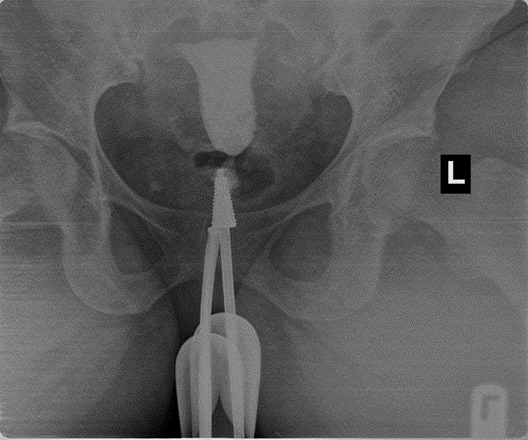

Figure 3: shows bilateral proximal tubal occlusion

The prevalence of tubal pathologies in this study was 29.7% with bilateral proximal tubal occlusion being the most common abnormality, accounting for 10% of cases. This finding corroborates studies conducted in Lagos20 and Oghara21, where similar patterns were reported. However, a study in Zaria22 found unilateral tubal occlusion to be more common. Among unilateral cases, right sided blockages (5.7%) were more prevalent than left sided (2.6%), consistent with findings in Sokoto15 and Lagos20. Conversely, studies in Maiduguri16 and Korle-Bu14 reported left sided predominance. Some cases of bilateral proximal tubal occlusion were presumably due to tubal spasm; in this study all patients had intramuscular injection of hyoscine bromide (Buscopan) at the beginning of the procedure which is thought to prevent spastic tubal occlusion.